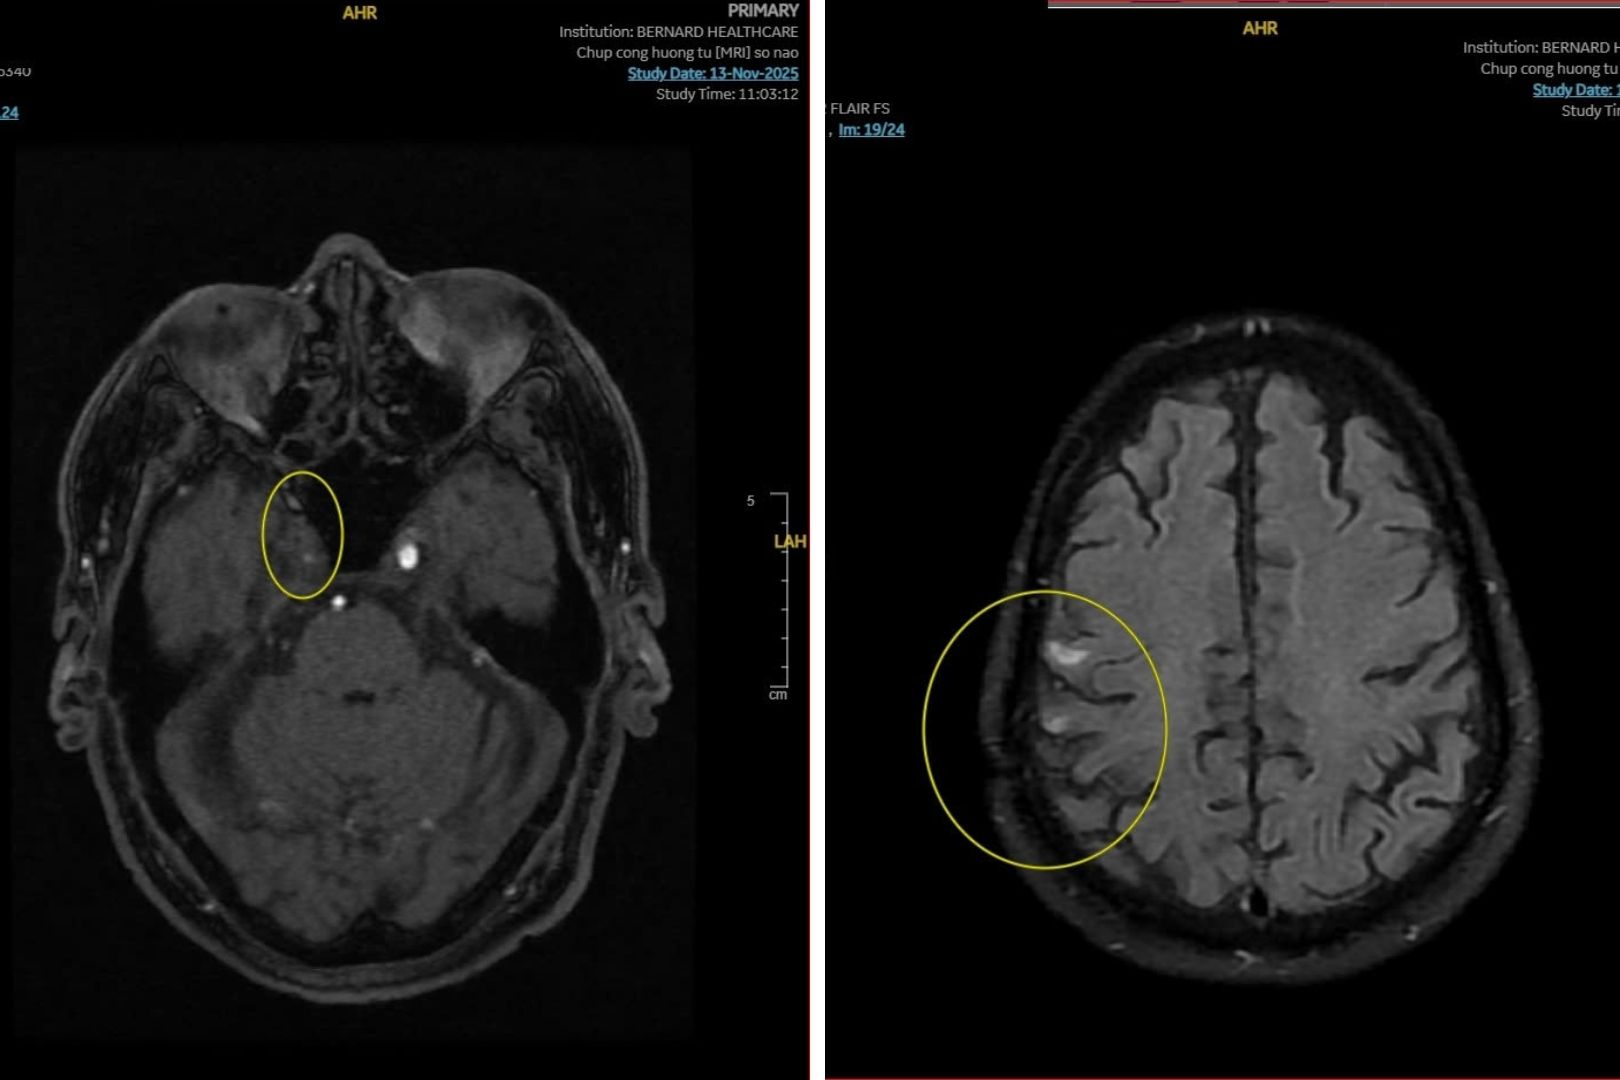

Kết quả MRI sọ não của bệnh nhân cho thấy nhiều bất thường nghiêm trọng. Đầu tiên là bệnh lý mạch máu nhỏ (Fazekas 2) với nhiều ổ tăng tín hiệu chất trắng dưới vỏ và quanh não thất hai bên. Các tổn thương bắt đầu hội tụ, phù hợp với hình ảnh thoái hóa mạch máu nhỏ. Đây là nguyên nhân phổ biến gây giảm trí nhớ, mất thăng bằng và đột quỵ nhồi máu nhỏ ở người lớn tuổi.

Vấn đề thứ hai là tắc động mạch cảnh trong (P) từ đoạn xương đá thể hiện qua tín hiệu hiệu dòng chảy qua đoạn M1 kém rõ nét. Đây là phát hiện quan trọng, vì tắc động mạch cảnh trong có thể gây đột quỵ thiếu máu não nếu không được theo dõi và xử trí phù hợp.

Ngoài ra, hình ảnh học còn ghi nhận mổ sọ đỉnh phải và màng bất thường tín hiệu dưới vỏ phù hợp tổn thương cũ - thoái hóa.